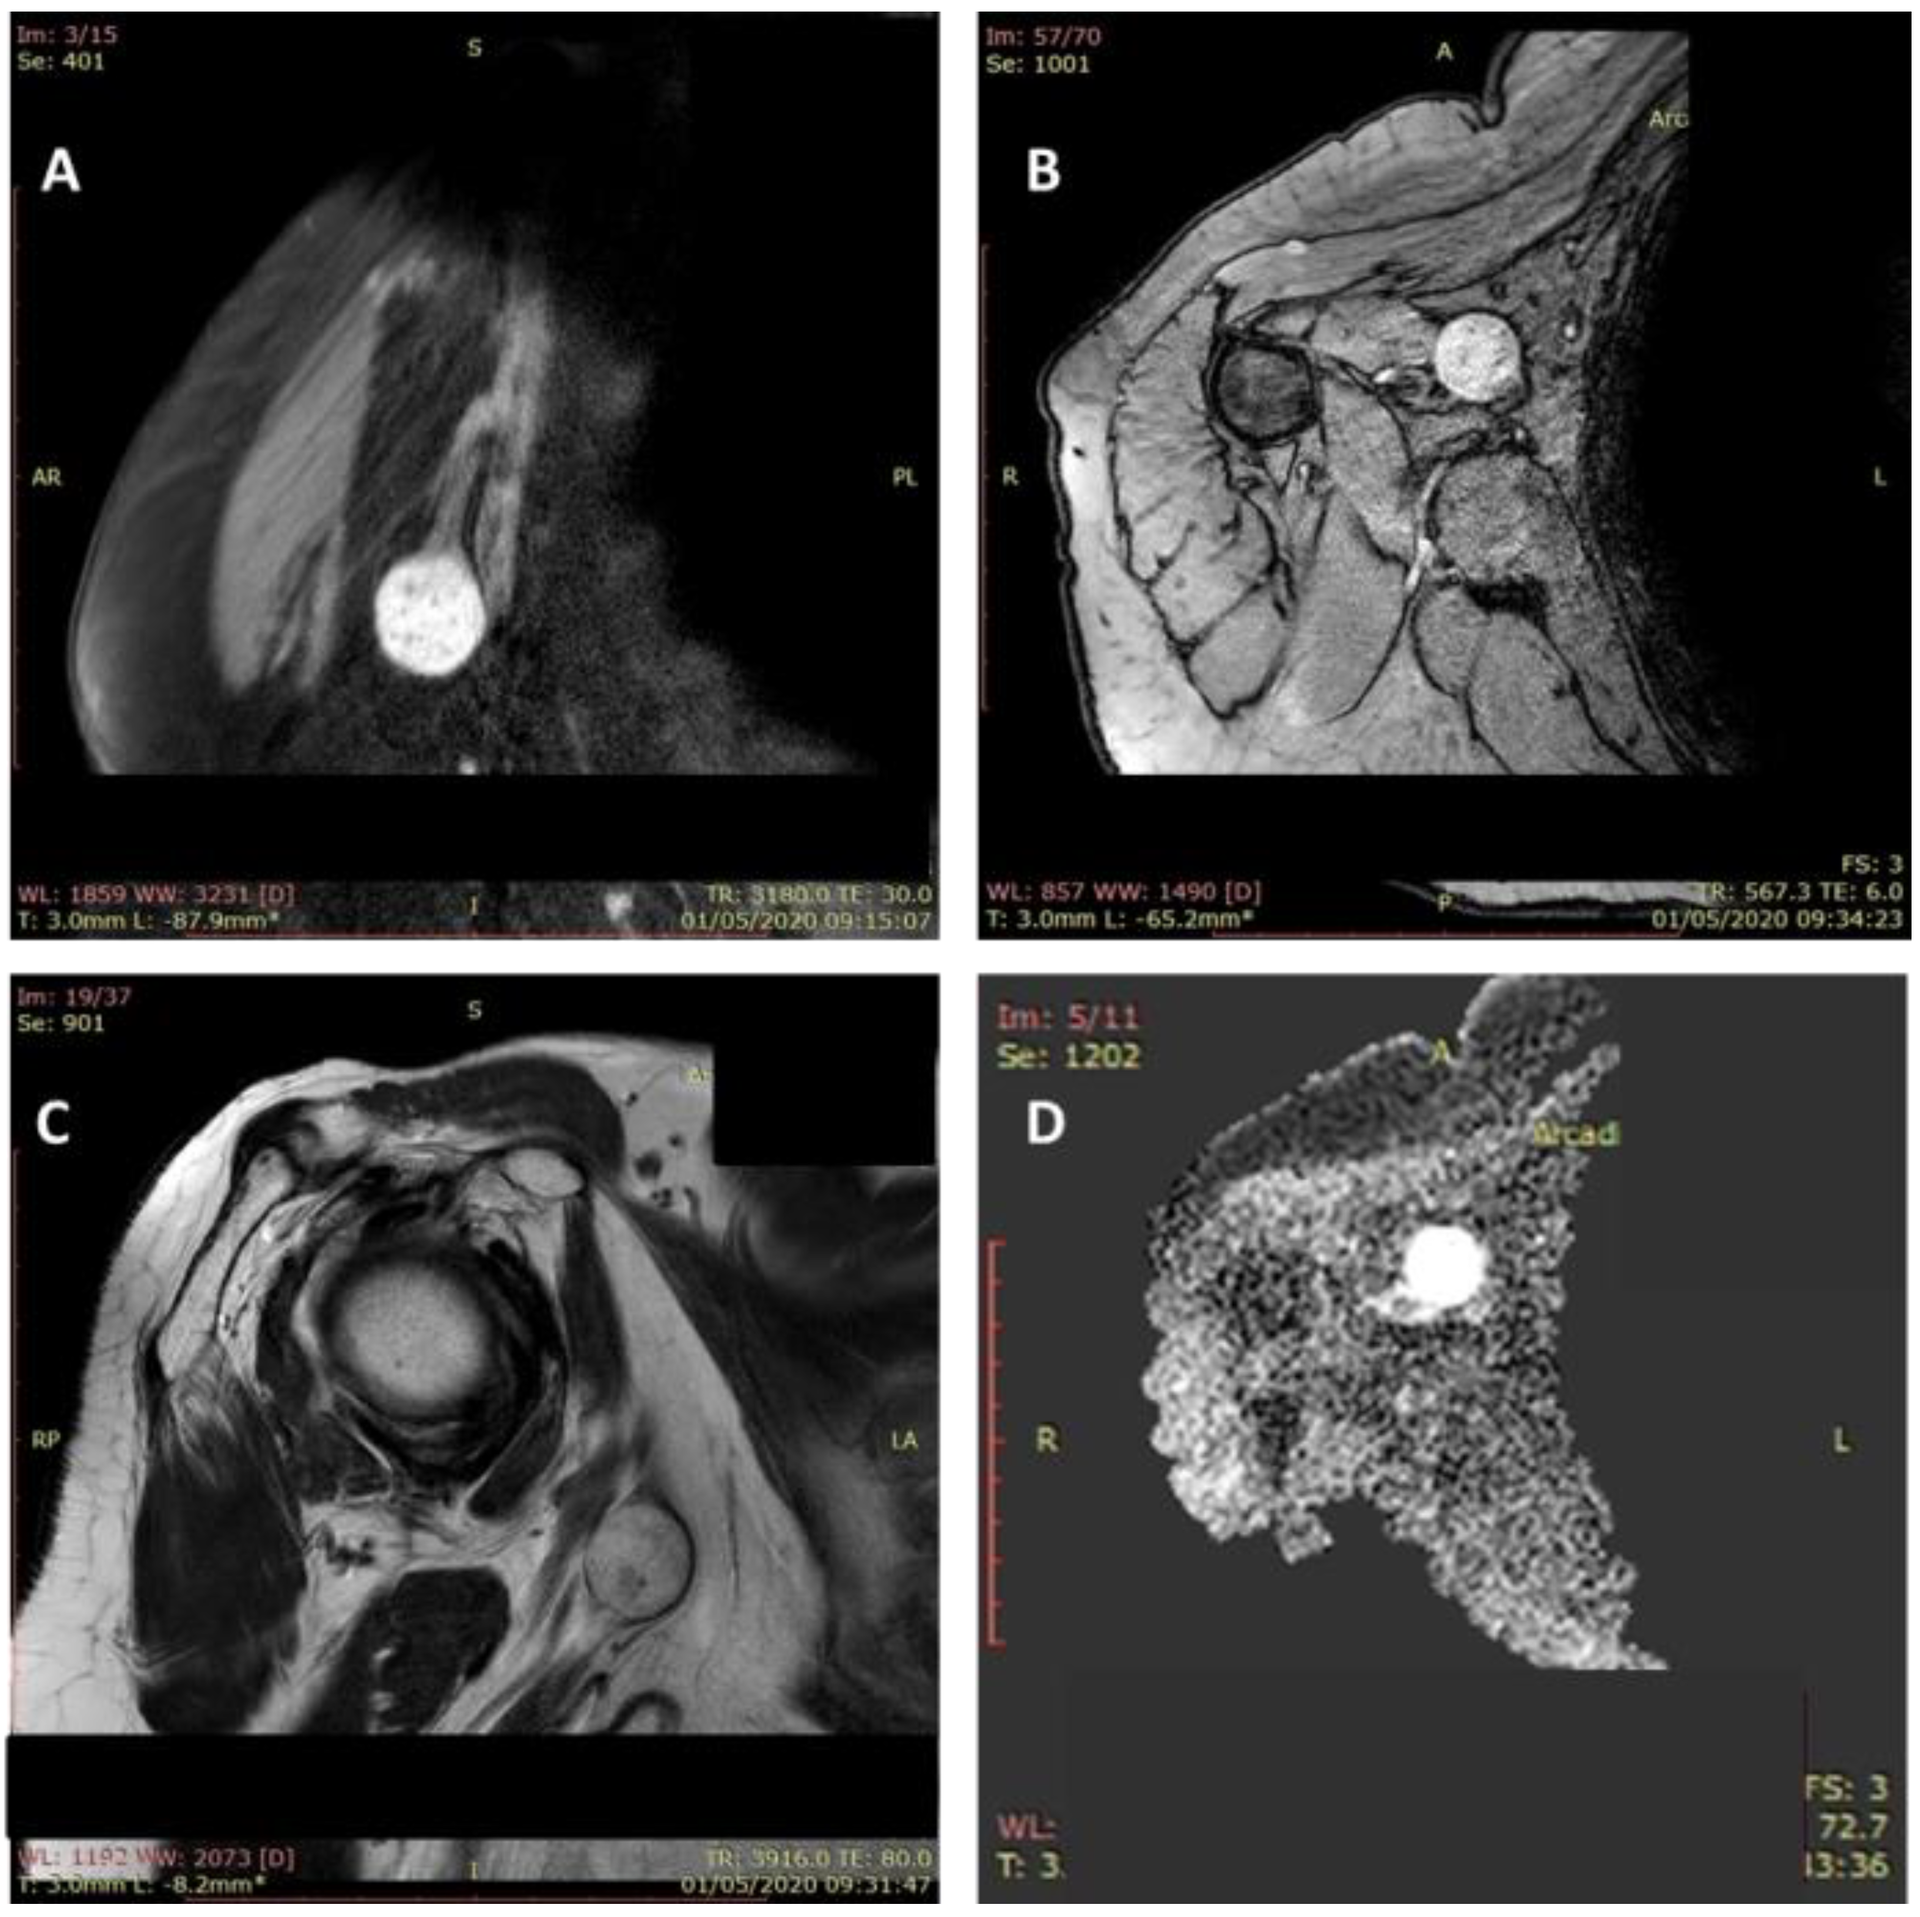

신경초종은 종종 지방종, 신경섬유종, 섬유종, 신경절 및 황색종과 오진되어 "혼동"될 수 있습니다. 신경초종을 진단하기 위해서는 초음파와  MRI 같은 영상 검사를 시행한다. 초음파 검사에서 신경초종은 일반적으로 균질하고 잘 정의된 저에코 종괴로 나타나며 MRI 검사에서는 T2 강조영상에서는 밝게 나타나기에 MRI 검사의 진단가치는 90% 이상 입니다.